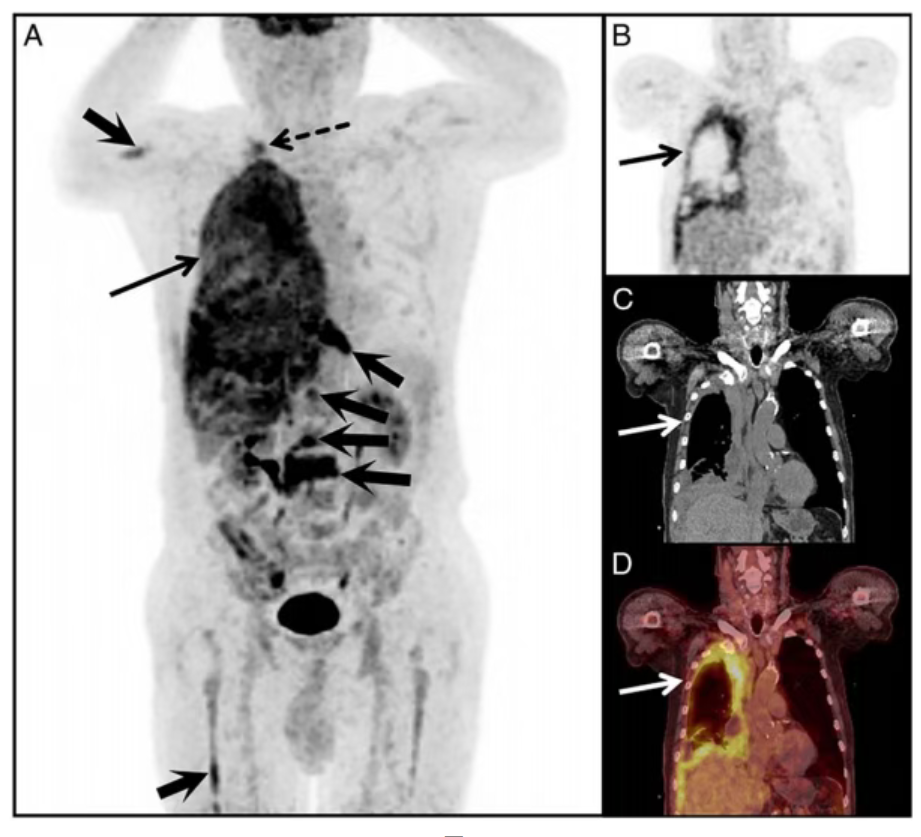

“热性胸膜”征是指胸膜在18F-FDG PET/CT显像中呈现弥漫性或局灶性氟代脱氧葡萄糖高摄取,且与CT显示的胸膜增厚区域完全对应的影像特征。这一征象传统上主要与常见恶性肿瘤相关,但最新临床实践表明,核医学医师需要拓宽其鉴别诊断思路。

核医学专家指出,当PET/CT显示单侧胸膜弥漫性FDG高代谢活性(SUVmax显著升高)并伴有多部位转移时,除常见病变外,应将USRCS等罕见肉瘤纳入鉴别体系。这一发现凸显了功能代谢影像在罕见肿瘤诊断中的独特价值。

18F-FDG PET/CT作为核医学领域的重要技术手段,通过追踪放射性核素标记的代谢底物在体内的分布,能够从分子层面揭示肿瘤的代谢活性。该技术不仅能精准显示病变范围和代谢负荷,还能为临床活检提供精确靶点定位,为后续的病理诊断和分期治疗提供关键依据。